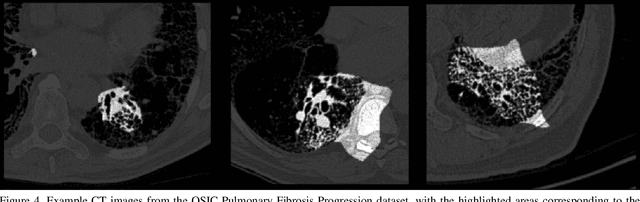

Abstract:Pulmonary fibrosis is a devastating chronic lung disease that causes irreparable lung tissue scarring and damage, resulting in progressive loss in lung capacity and has no known cure. A critical step in the treatment and management of pulmonary fibrosis is the assessment of lung function decline, with computed tomography (CT) imaging being a particularly effective method for determining the extent of lung damage caused by pulmonary fibrosis. Motivated by this, we introduce Fibrosis-Net, a deep convolutional neural network design tailored for the prediction of pulmonary fibrosis progression from chest CT images. More specifically, machine-driven design exploration was leveraged to determine a strong architectural design for CT lung analysis, upon which we build a customized network design tailored for predicting forced vital capacity (FVC) based on a patient's CT scan, initial spirometry measurement, and clinical metadata. Finally, we leverage an explainability-driven performance validation strategy to study the decision-making behaviour of Fibrosis-Net as to verify that predictions are based on relevant visual indicators in CT images. Experiments using the OSIC Pulmonary Fibrosis Progression Challenge benchmark dataset showed that the proposed Fibrosis-Net is able to achieve a significantly higher modified Laplace Log Likelihood score than the winning solutions on the challenge leaderboard. Furthermore, explainability-driven performance validation demonstrated that the proposed Fibrosis-Net exhibits correct decision-making behaviour by leveraging clinically-relevant visual indicators in CT images when making predictions on pulmonary fibrosis progress. While Fibrosis-Net is not yet a production-ready clinical assessment solution, we hope that releasing the model in open source manner will encourage researchers, clinicians, and citizen data scientists alike to leverage and build upon it.